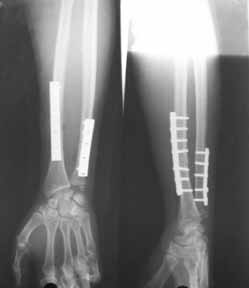

Middle aged adult hospital employee invoved in a road traffic accident. Suffered closed hip dislocation left side and fracture both bones right forearm(ulna compound) Underwent closed reduction of right hip and debridement with ORIF of forearm. Pre op X-ray showed acetabular rim fracture and post op X-ray showed a suspicious fracture line through the head of femur. One fragment of acetabulum seen displaced. CT done subsequently shows an undisplaced fracture through the head of femur with the acetabular rim fracture which is displaced.

1) Posterior aproach to fix the acetabular rim and fix the head fracture simultaneosly. To fix the fracture from the trochanter the problem will be the width of the proximal fragment (less than 1.45 cm in the maximum width - measured from CT monitor). This means that I cannot lag the fragment from the trochanter. In fact if I try for that the fragment could get displaced. Other option was to consider fixation from the head while fixing the posterior lip and countersink the screw head.